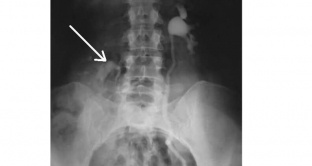

- excretory urography - performed in a horizontal and vertical position, allows you to determine the displacement of the kidney due to its relationship to the vertebrae. Normal mobility of the kidneys is the height of the body of a maximum of one and a half vertebrae;